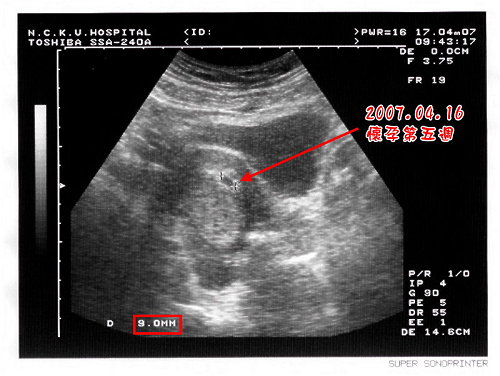

在得知老婆已經懷孕時,大約是懷孕五週時,當時超音波所照到的胚胎還只有豆子一般大,而老婆也還沒有明顯的孕吐現象。其實只要注意營養,懷孕初期也不會對日常生活有太大的影響。